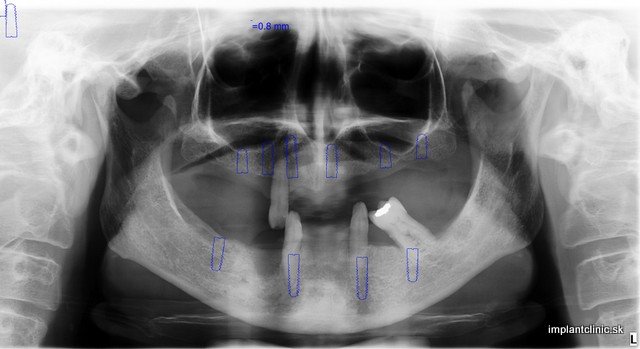

Takto sa vyjadrila o Implant Clinic Vendy. Podstúpila zákrok, ktorý vyžadoval dvojitú dostavbu kosti, 10 zubných implantátov a 24 implantátových koruniek. Ak zuby chýbajú dlhšiu dobu môže dojsť k úbytku kosti. Resorpciou kosti strácajú mäkké tkanivá oporu, čím môže Vaša tvár nadobudúť starší vzhľad.

Umiestnením zubných implantátov do čeľustnej kosti predchádzame tomuto procesu, pretože podobne ako Vaše vlastné zuby aj zubné implantáty prenášajú žuvacie sily na okolitú kosť, čo ju stimuluje a tým sa predchádza úbytku kosti. V niektorých prípadoch ako u Vendy bola potrebná dostavba kosti. Mnoho ľudí má mýlnu mienku o tomto zákroku a myslia si, že je to zložitý proces.